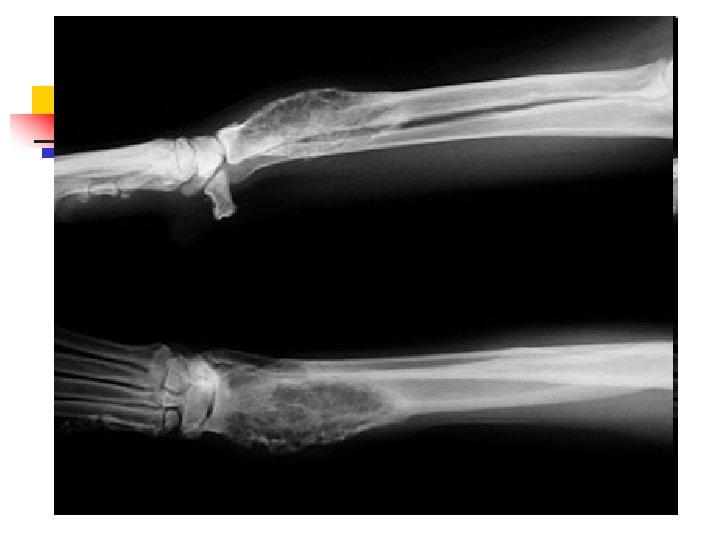

When Animals Limp n n n The good new is that 9 out of 10 limping animals have what we call soft tissue injuries a sprain, a pull, a bruise and only require exercise restriction to heal. However, 1 out of 10 animals with lameness has something more serious, and we can tell which ones by close observation of the patient walking and careful physical examination. In those cases, radiographs are used to make a diagnosis.

When Lameness isn’t Simple n n Sometimes when an animal limps the cause turns out to be something more serious than a simple injury. The doctors palpated a firm, painful lump in the leg this dog was favoring. Radiographs showed that the bone was expanded in that area, with a motheaten, hollowed-out center. These are classic signs of a tumor in the bone, known as an osteosarcoma.